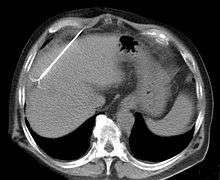

RFA may be performed to treat tumors in the lung,[4][5][6] liver,[7] kidney, and bone, as well as other body organs less commonly. Once the diagnosis of tumor is confirmed, a needle-like RFA probe is placed inside the tumor. The radiofrequency waves passing through the probe increase the temperature within tumor tissue and results in destruction of the tumor. RFA can be used with small tumors, whether these arose within the organ (primary tumors) or spread to the organ (metastases). The suitability of RFA for a particular tumor depends on multiple factors.